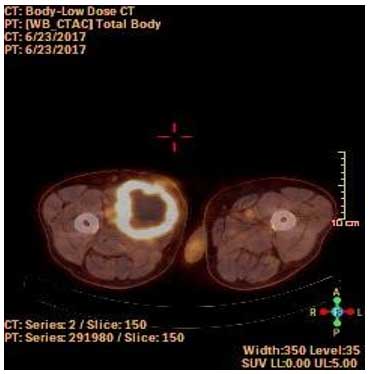

If leiomyosarcoma is diagnosed, a CT scan or PET-CT is performed for screening purposes to detect metastases (often to the lungs). Multiple localizations may be detected at the time of leiomyosarcoma diagnosis.